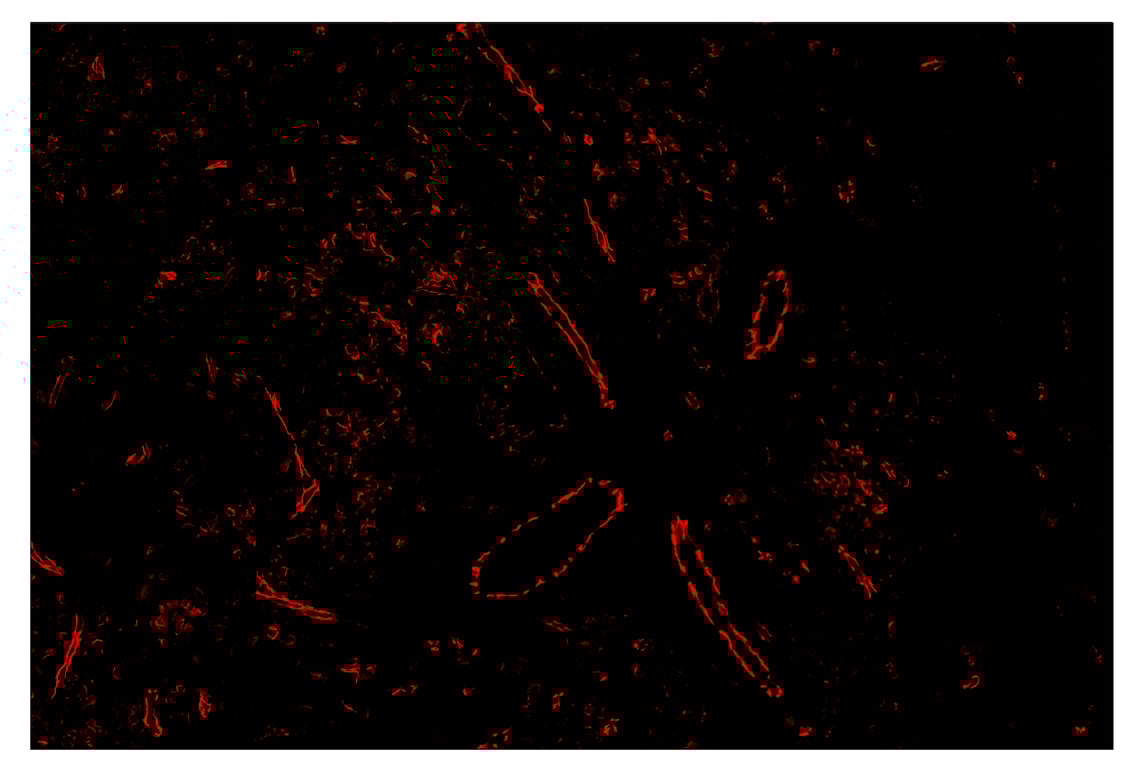

Immunohistochemistry Image 1: CD31 (PECAM-1) (89C2) & CO-0028-488 SignalStar<sup>™</sup> Oligo-Antibody Pair

SignalStar™ immunohistochemical analysis of paraffin-embedded human gastric adenocarcinoma using CD31 (PECAM-1) (89C2) & CO-0028-488 SignalStar™ Oligo-Antibody Pair #83823 (green). All fluorophores have been assigned a pseudocolor, as indicated. Staining was performed on the BOND RX by Leica Biosystems.